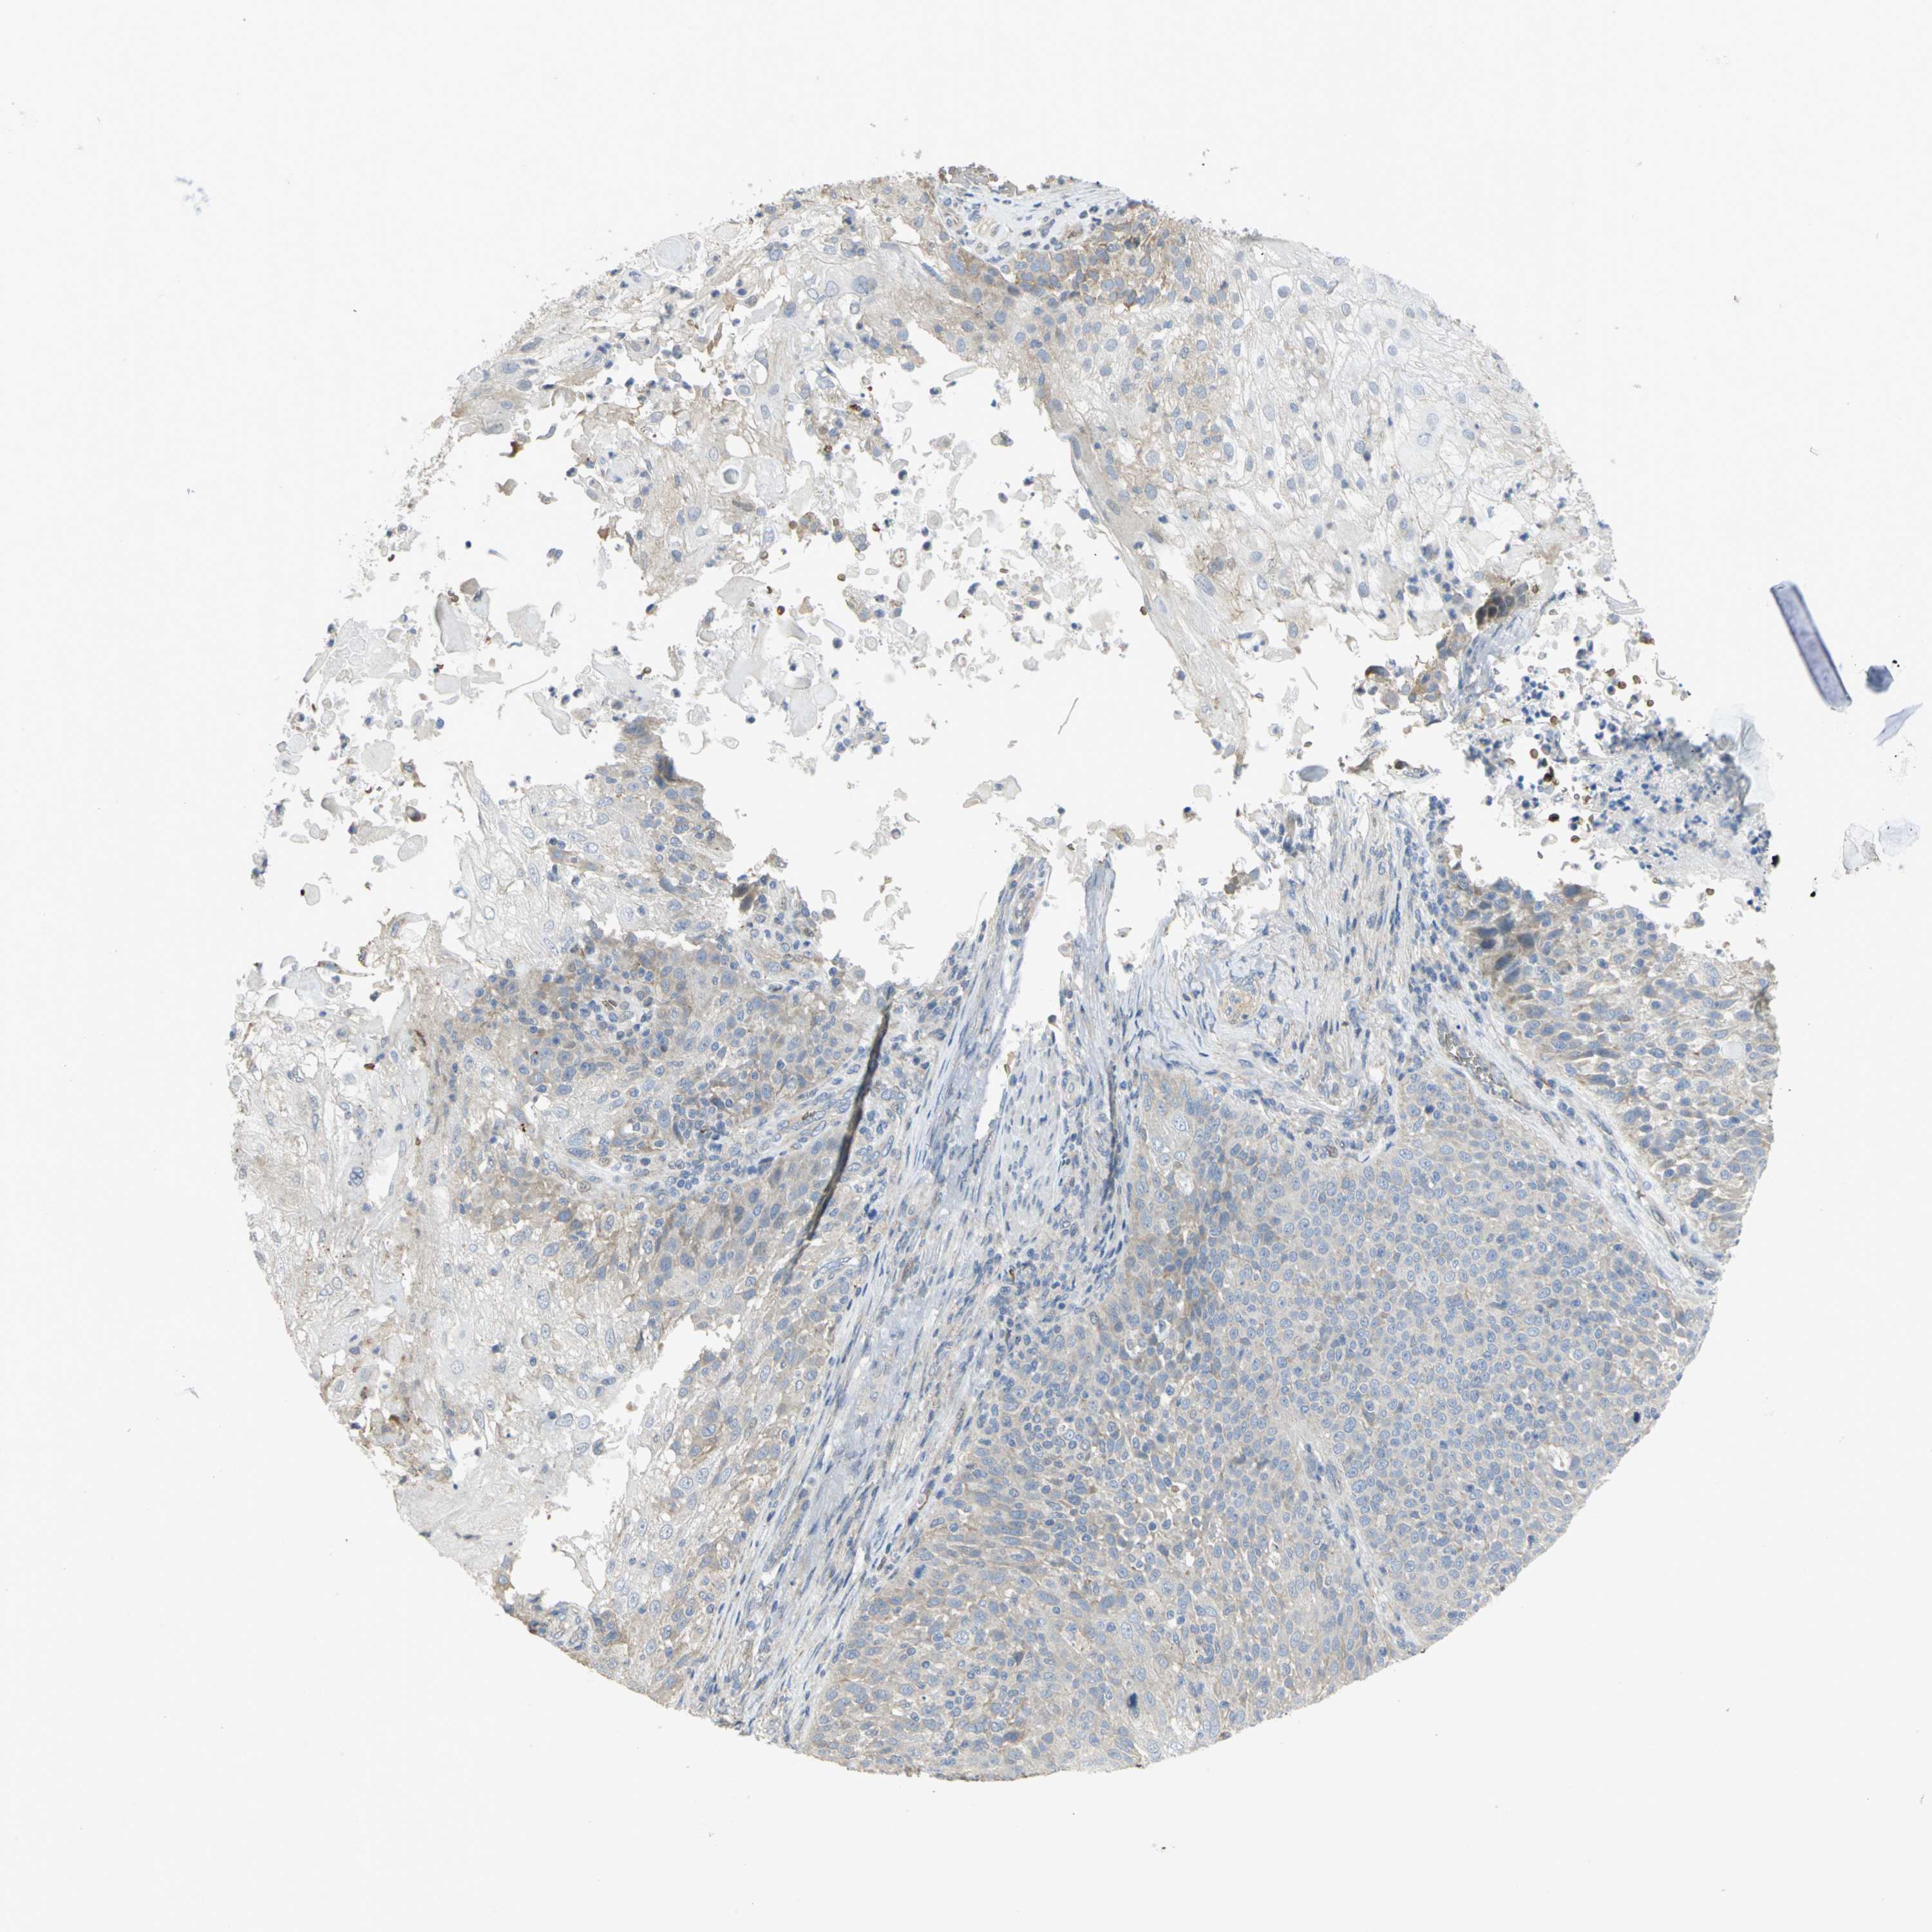

SKIN CANCER - Protein expressioni

A mouse-over function shows sample information and annotation data. Click on an image to view it in a full screen mode. Samples can be filtered based on level of antibody staining by selecting one or several of the following categories: high, medium, low and not detected. The assay and annotation is described here.

Antibody stainingi

Antibody staining in the annotated cell types in the current human tissue is reported as not detected, low, medium, or high, based on conventional immunohistochemistry profiling in selected tissues. This score is based on the combination of the staining intensity and fraction of stained cells.

Each image is clickable and will lead to virtual microscopy that enables deeper exploration of all samples and also displays staining intensity scores, fraction scores and subcellular localization as well as patient and tissue information for each sample.

Antibody HPA004842

Antibody HPA056953

Staining

High

Medium

Low

Not detected

Intensity

Strong

Moderate

Weak

Negative

Quantity

>75%

75%-25%

<25%

None

Location

Nuclear

Cytoplasmic/membranous

Cytoplasmic/membranous,nuclear

Squamous cell carcinoma, NOS

Basal cell carcinoma